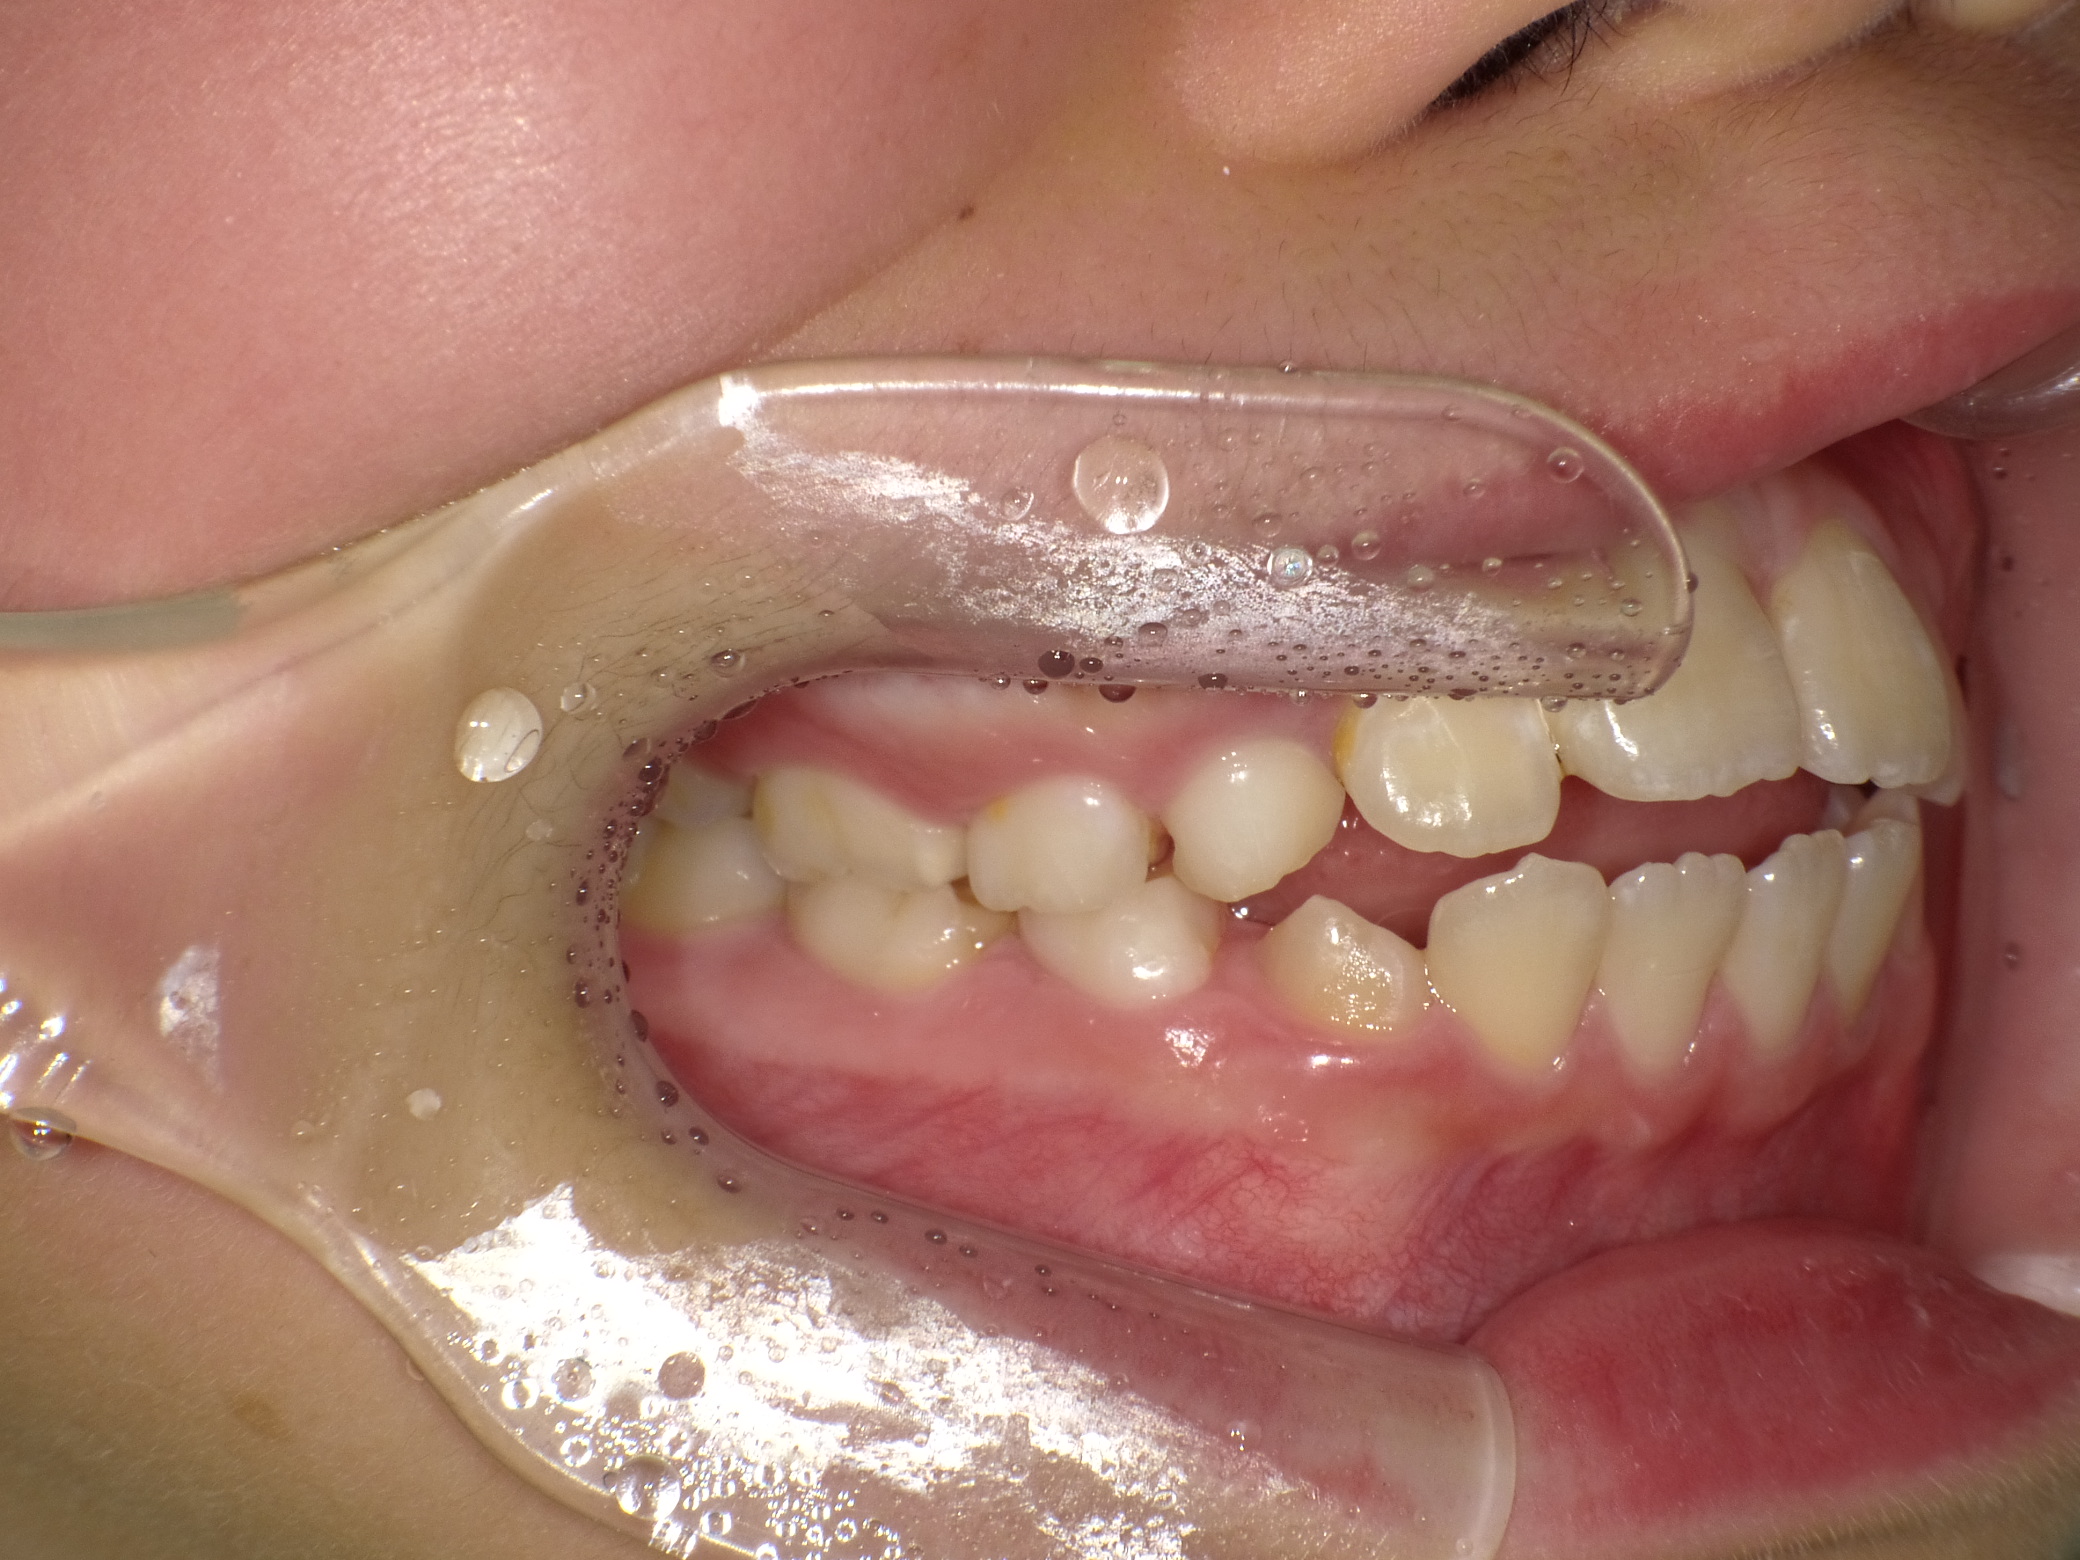

【小学生】マイオブレース矯正 開咬を改善

小学生で開始

マイオブレース

出っ歯

開咬

非抜歯

1期治療のみで改善

Before

After

治療期間

2年

治療開始

8歳

種類

マイオブレース矯正

使用装置

コメント

マイオブレースと 口腔筋機能療法で 咬み合わせが改善しました。

その後 装置を何も付けていませんが 後戻りしていません。

舌癖がある場合、後戻りしやすいですが、

口腔筋機能療法をきっちり取り組んでくれたので

リテーナーなど何も使用せずに安定しています。(AFTERの写真は5年後)